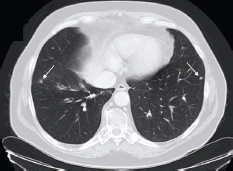

Approximately, five years after surgery, due to an increase in PSA level (4.3 ng/ml), an abdominal and pelvic CT scan was performed. On the lower thoracic images, non-specific micronodules in the lower lobe of his right lung were documented (Figure 1).

Figure 1. Patient #1. Thoracic CT scan documenting micronodules in the right and left lungs (lower lobes). Arrows indicate secondary lesions.